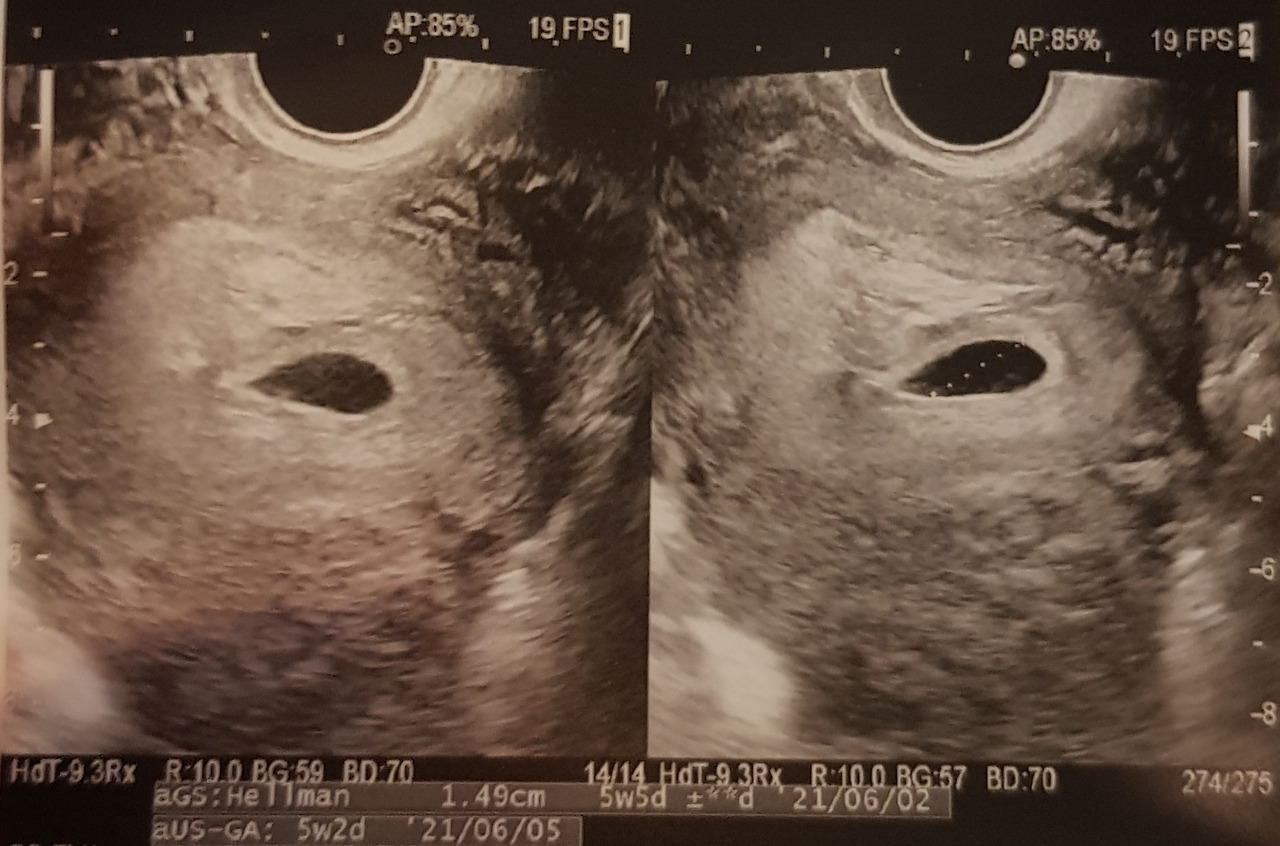

그런데 튼튼이는 주수보다 조금 느린 것 같았다. 임테기의 진하기나, 착상혈이 나온 시기나, 아기집을 본 시기나 크기나 등등의 것들이.

난임 병원에서 말하는 주차별 공식이 있었다. 5주 차 아기집, 6주 차 난황, 7주 차 심장소리. 시험관으로 착상이 성공하면 이 순서대로 진행이 되어야 된다고 했다. 그런데 나는 5주 차 말에 간신히 턱걸이로 아기집을 봤지 않았던가. 그땐 턱걸이로라도 넘어가면 됐지 라고 생각했지만 마음 한편이 불안하지 않은 것은 아니었다.

한참을 기다려서 들어간 초음파실에서는 아기집이 잘 자랐는데 비어있다고 했다.

빈집인 초음파 사진과 임신확인서를 받아 들고 보건소로 가는 길에 창피하게도 버스에서 자꾸 눈물이 났다. 남편은 그냥 튼튼이가 좀 늦는 거라고 했지만 여자들은 감이라는 게 있다. 아. 이젠 진짜 아닌가 보다.

의사 선생님과 같이 본 초음파의 아기집은 여전히 비어있었다. 하물며 크기가 어제보다 작다고 했다. 이런 경우에는 자연도태가 진행되는 거란다. 다음 주 초음파에서는 더 나빠질 가능성이 높고, 지금 출혈 자체가 없는 상태라서 자연 배출은 어려워 보이니 아마 수술을 해야 될 거라고. 임신 증상도 여전하고 입덧도 아직 있는데 자연도태 중이라니.